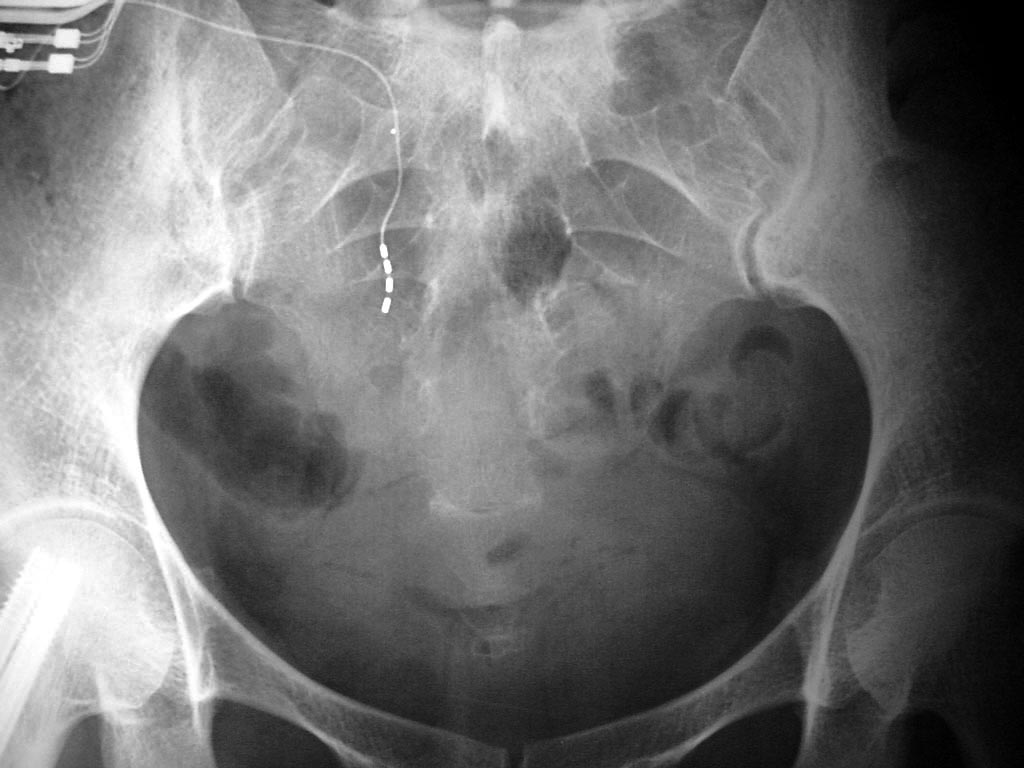

Sacral stimulator AP and lateral views |

Sacral stimulator (AP view) |

This is a different patient than the preceding two images. From Hunter, 2004 |